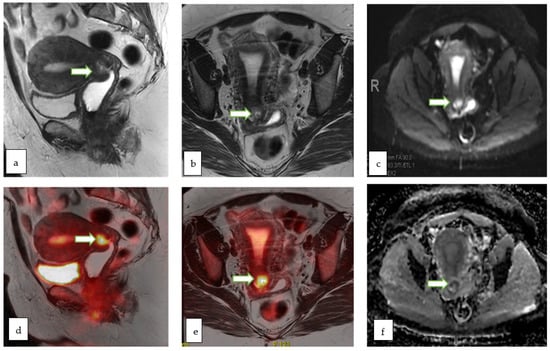

| O-RADS MRI Score | Risk Category | Positive Predictive Value for Malignancy | Lexicon Description |

| 3 | Low risk | ~5% | Cyst: Unilocular–proteinaceous, hemorrhagic or mucinous fluid content - Smooth enhancing wall - No enhancing solid tissue |

| Cyst: Multilocular-Any type of fluid, no lipid content - Smooth septae and wall with enhancement-No enhancing solid tissue | |||

| Lesion with solid tissue (excluding T2 dark/DWI dark) - Low risk time intensity curve on DCE MRI | |||

| Dilated fallopian tube - Non-simple fluid: Thin wall/folds - Simple fluid: Thick, smooth wall/folds - No enhancing solid tissue | |||

| 4 | Intermediate risk | ~50% | Lesion with solid tissue (excluding T2 dark/DWI dark) - Intermediate risk time intensity curve on DCE MRI - If DCE MRI is not feasible, score 4 is any lesion with solid tissue (excluding T2 dark/DWI dark) that is enhancing ≤ myometrium at 30–40 s on non-DCE MRI |

| Lesion with lipid content - Large volume enhancing solid tissue | |||

| 5 | High risk | ~90% | Lesion with solid tissue (excluding T2 dark/DWI dark) - High risk time intensity curve on DCE MRI - If DCE MRI is not feasible, score 5 is any lesion with solid tissue (excluding T2 dark/DWI dark) that is enhancing > myometrium at 30–40 s on non-DCE MRI |

| Peritoneal, mesenteric or omental nodularity or irregular thickening with or without ascites |